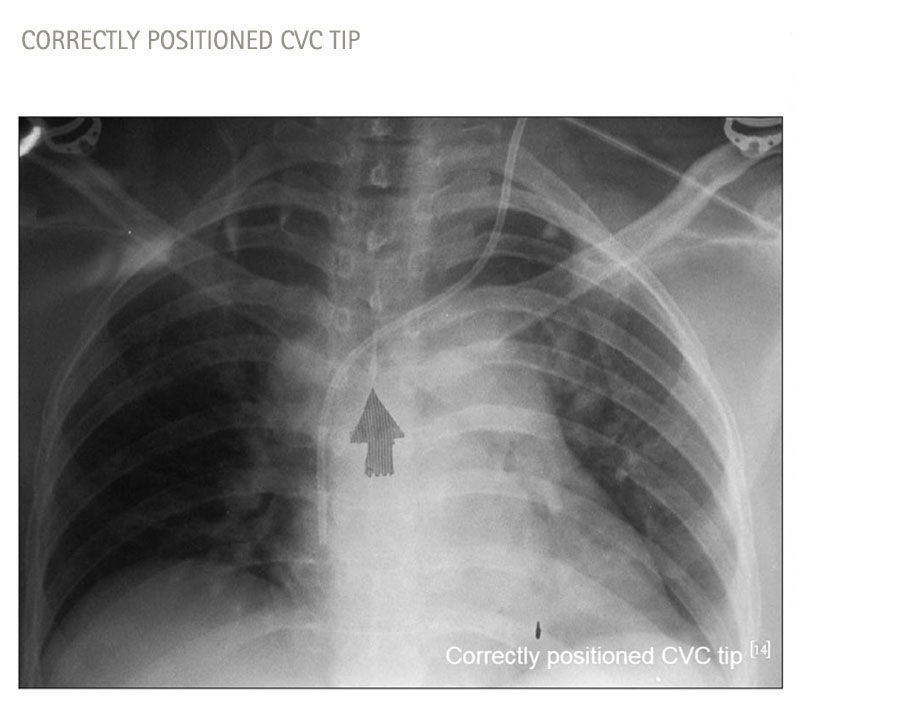

Correct catheter tip positioning6

„ [...] correct position of the catheter has to be ensured during placement"

scheme of catheter tip position Caers J, Fontaine C,Vinh-Hung V et al (2005) Catheter tip position as a risk factor for thrombosis associated with the use of subcutaneous infusion ports. Support Care Cancer 13:325-331​

Why is it important to achieve an "ideal" catheter tip location for CVC, TIVAD and PICC?

• Infusion of vasopressors, irritant drugs, or parenteral nutrition requires maximal dilution,  avoiding mixing of multiple drugs such as chemo- and antibiotic therapy and blood sampling

• Extracorporeal circuits, e.g. dialysis requires a very high blood flow rate passing by the catheters, and separation of inflow and outflow of catheters to avoid blood recirculation

• Measurement of ScvO2 requires catheter tip lies in or as close to the right atrium as possible